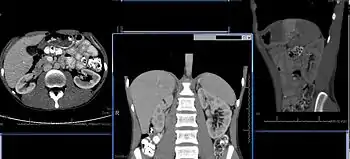

تتواجد الكلى عند الإنسان في جوف البطن، واحدة على كل جانب من العمود الفقري تحت الحجاب الحاجز، حيث تتواجد بزاوية مائلة قليلًا خلف الصفاق.[1] عدم التماثل داخل جوف البطن، الناجم عن موقع الكبد، يؤدي عادةً أن تكون الكلية اليمنى منخفضة أكثر وأصغر بشكل قليل مقارنةً باليسرى، وتتواجد أقرب إلى الوسط بشكل طفيف مقارنة بالكلية اليسرى.[2][3] تقع الكلية اليسرى تقريبًا على مستوى الفقرة الصدرية الثانية عشر (T12) حتى الفقرة القطنية الثالثة (L3)،[4] واليمنى منخفضة أكثر بشكل قليل. تجلس الكلية اليمنى تحت الحجاب الحاجز وخلف الكبد. أما الكلية اليسرى فتجلس أسفل الحجاب الحاجز وخلف الطحال. فوق كل كلية توجد غدة كظرية. يحمي الضلعين الـ 11 والـ 12 بشكل جزئي الأجزاء العليا لكل كلية. يحيط كل كلية والغدة الكظرية المرافقة لها طبقتين من الدهون، الدهن المحيط بالكلية والدهن المجاور للكلية، واللفافة الكلوية. في الذكور البالغين، تزن الكلية بين 125 و170 غرام. أما الإناث فتزن الكلية ما بين 115 و155 غرام.[5]